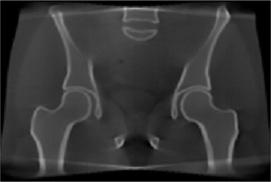

There is growing concern on the radiation dose delivered to patient during CT or cone-beam CT (CBCT) procedure, especially for pediatric patients, screening, or repeated acquisitions for CBCT-guided radiation therapy over a whole treatment course. We have developed various strategies to enhance image quality of low-dose CT and CBCT.

On-board imaging can provide updated patient information at the treatment position thus can be potentially used for adaptive radiation therapy. On-board imaging is often degraded by various artifacts, which makes it challenging for  quantitative applications. We are interested in the development of quantitative imaging techniques for their applications in image-guided and adaptive radiation therapy. One of our recent research focuses is on the development and evaluation of a quantitative CBCT technique.

We developed a moving-blocker-based approach that is able to suppress the scatter-related artifacts, reduce the imaging dose, and simultaneously obtain complete volumetric information within the field of view using a single CBCT scan.